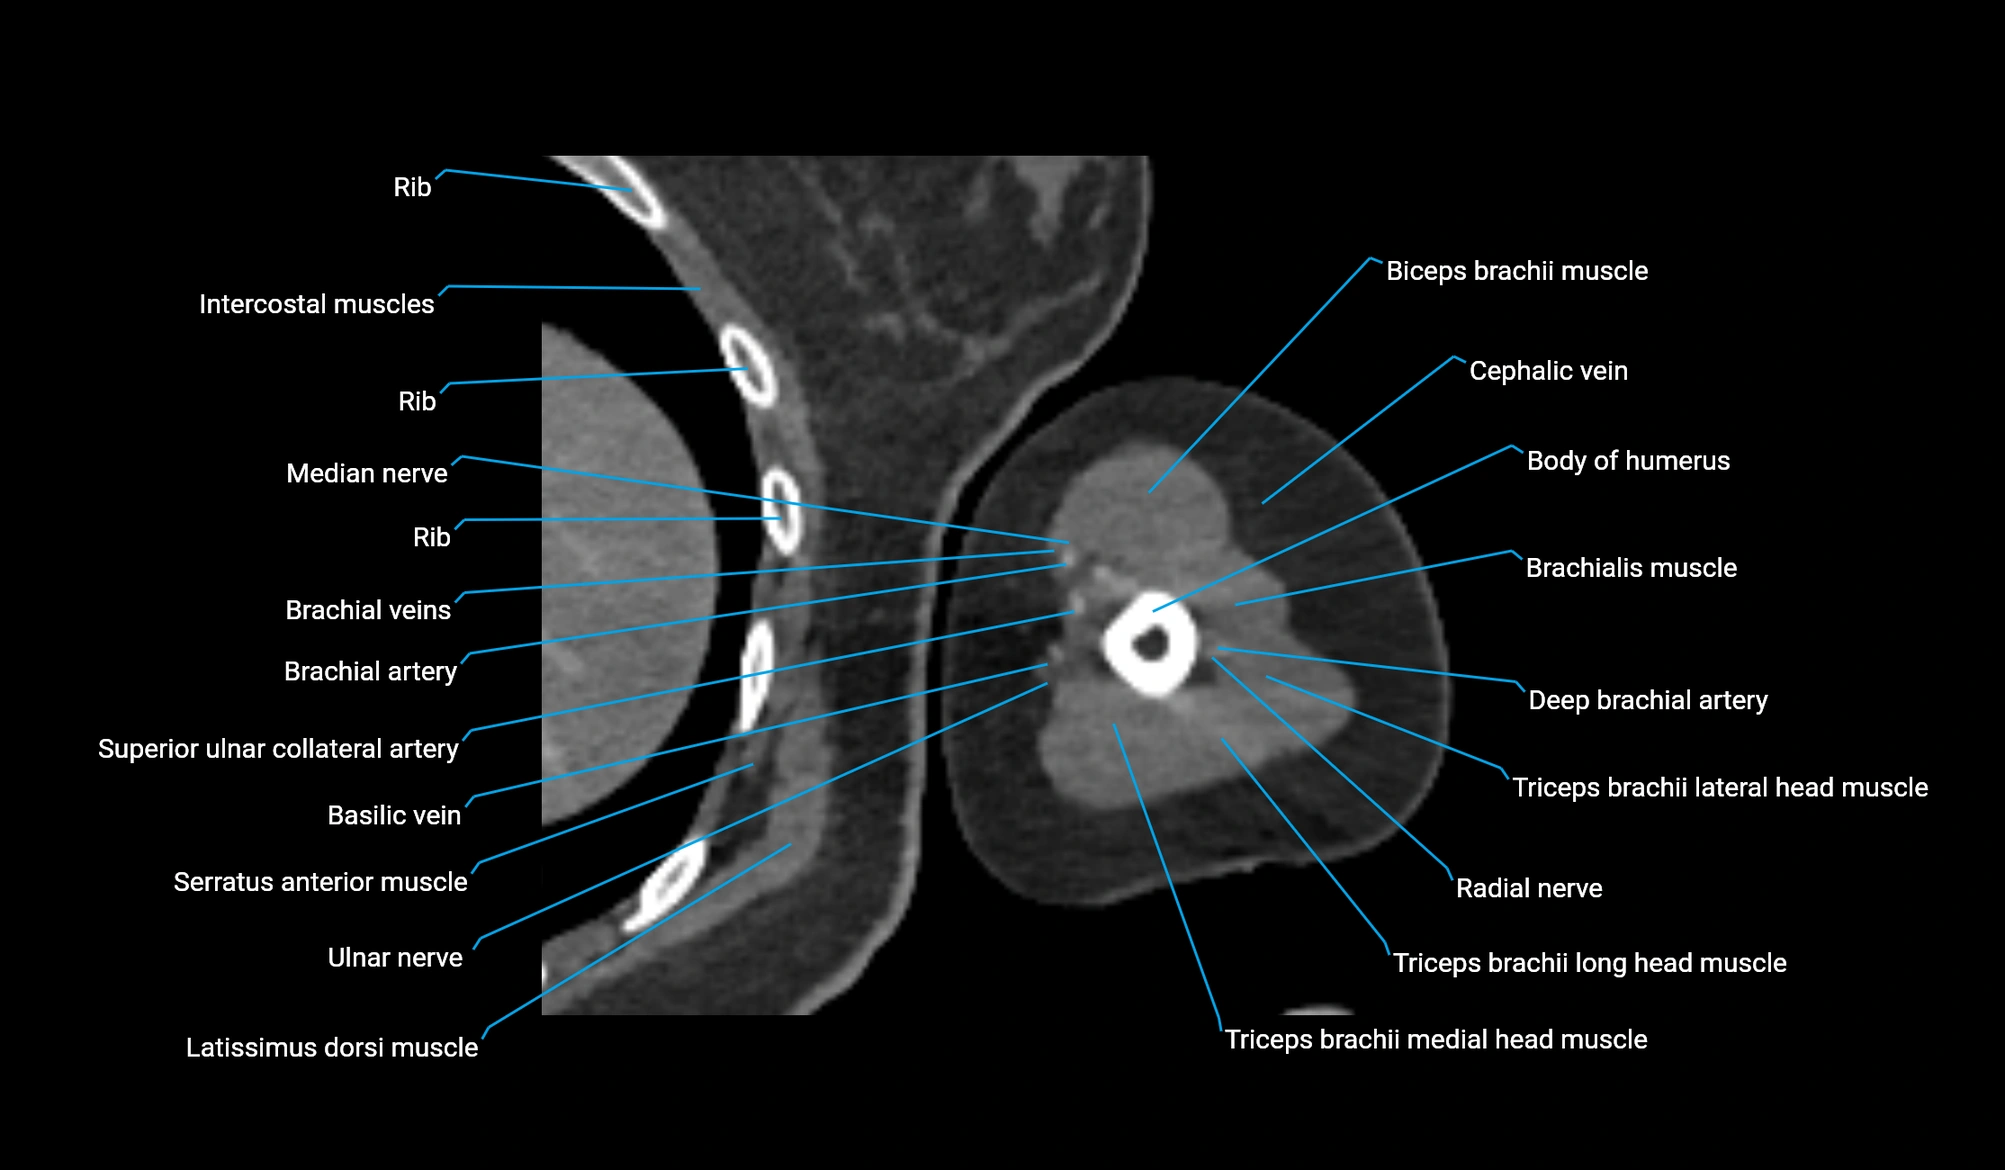

- Body of humerus

- Brachial artery

- Brachialis muscle

- Cephalic vein

- Deep brachial artery

- Long head of triceps brachii muscle

- Median nerve

- Radial nerve

- Superior ulnar collateral artery

- Ulnar nerve